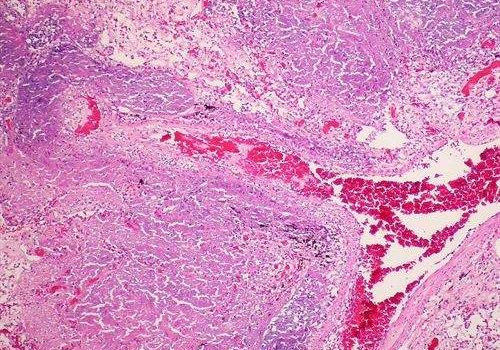

Vitamina C poderia acabar com tuberculose resistente a medicamentos

Um experimento realizado com cultivos de laboratório identificou que a vitamina C pode matar as bactérias de tuberculose resistentes a medicamentos (TB). Esta descoberta abre novas portas para pesquisas posteriores. “Não sabemos se a vitamina C funciona nos seres humanos, mas agora temos uma base racional para fazer um ensaio clínico. Também ajuda porque sabemos que a vitamina C é barata, amplamente disponível e muito segura de usar. Pelo menos, este trabalho nos mostra um novo mecanismo que podemos explorar para atacar a tuberculose”, manifestou William Jacobs, diretor do estudo e professor de Microbiologia, Imunologia e Genética da Universidade de Yeshiva, em Nova York, nos Estados Unidos. Ler mais